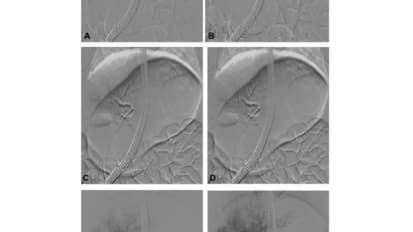

Endoscopic Ultrasound Measures Pressure in Hepatic Portal Vein

Gaining access to the liver through the stomach, Olaya Brewer Gutierrez and her therapeutic endoscopy colleagues at Johns Hopkins use endoscopic ultrasound to obtain a direct reading of the pressure in the hepatic portal vein.